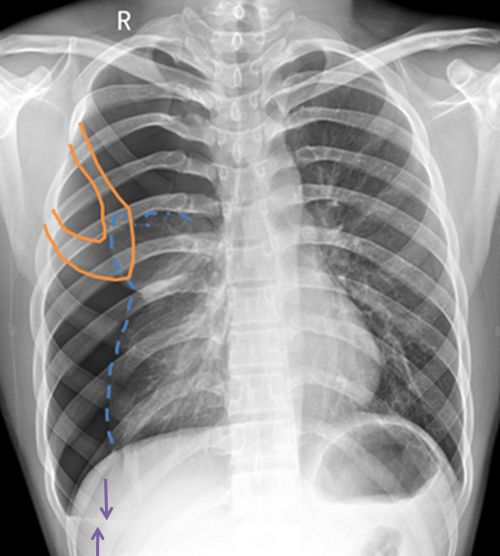

病例3患者的X线胸片

右上肺野见异常透亮无肺纹理区,内缘可见发线状肺组织压缩边缘,肺叶被压缩约30%(蓝色箭头)。心影及纵隔向对侧轻度移位(蓝色直线)。两膈面光滑,肋膈角锋利。